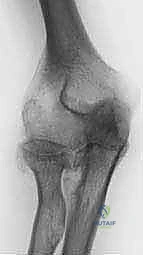

1. التخطيط الجراحي المسبق (Pre-operative Planning)

يتم إجراء صور أشعة سينية دقيقة (X-rays) وأحياناً تصوير مقطعي (CT Scan) لتقييم حجم العظام المتبقية وجودتها. في مرضى الروماتويد، يكون العظم غالباً هشاً (Osteoporotic)، مما يتطلب تخطيطاً دقيقاً لاختيار حجم ونوع المفصل الصناعي المناسب (مفصل متصل Linked أو غير متصل Unlinked).